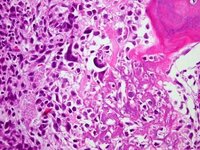

Osteossarcoma osteoblástico; osteoide em forma de rede em estroma sarcomatoso altamente pleomórfico

Do acervo do Dr. Michael J. Klein e da Dra. Luminita Rezeanu